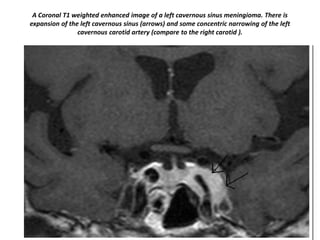

A Coronal T1 weighted enhanced image of a left cavernous sinus meningioma. There is

expansion of the left cavernous sinus (arrows) and some concentric narrowing of the left

cavernous carotid artery (compare to the right carotid ).

A Coronal T1weighted enhanced image of a left cavernous sinus meningioma. There is expansion of the left cavernous sinus (arrows) and some concentric narrowing of the left cavernous carotid artery (compare to the right carotid ).